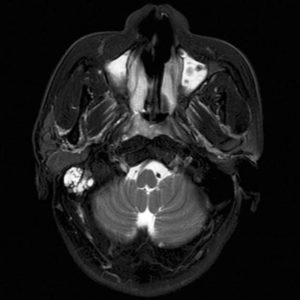

U dây VIII

Lượt xem: 162» 02-03-2019 -

U dây VIII

Lượt xem: 132» 24-11-2018 -

U dây VIII

Lượt xem: 130» 24-11-2018 -

U dây VIII

Lượt xem: 153» 24-11-2018 -

U dây VIII

Lượt xem: 147» 24-11-2018 -

U dây VIII

Lượt xem: 117» 24-11-2018 -

U dây VIII

Lượt xem: 149» 24-11-2018 -

U dây VIII

Lượt xem: 143» 24-11-2018 -

U dây VIII

Lượt xem: 158» 24-11-2018